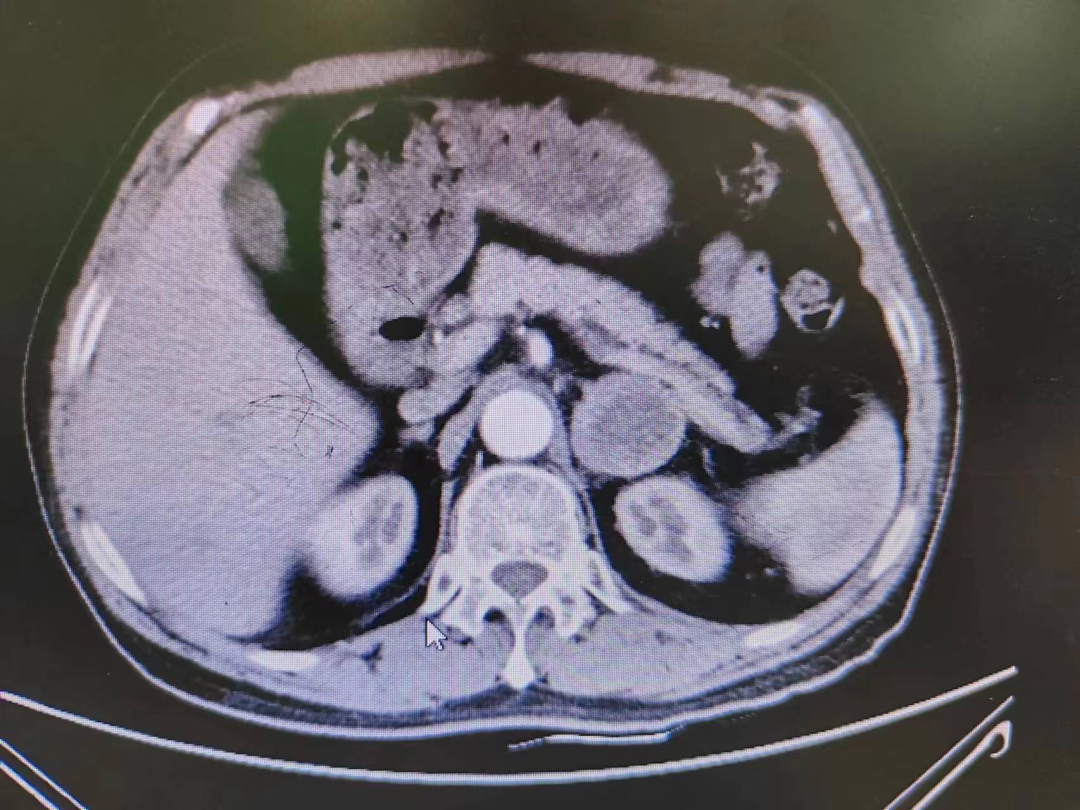

患者熊XX,67歲,因發現頭暈、頭痛曾多次于外院就診,到新橋醫院就診完善腎上腺CT考慮嗜鉻細胞瘤,既往有高血壓病史3年,血壓更高達230/120mmHg。我院高新區院區開診后,患者慕名而來。術前積極完善血尿兒茶酚胺代謝產物(MNS)均明顯升高,患者于我院高新區院區及江南院區泌尿外科積極控制血壓、心率、血糖,術前充分擴容。

因腫瘤位置位于腎蒂周圍,術中觸碰腫瘤導致血壓明顯升高,血壓波動較大,腫瘤表面血供豐富,不僅需要手術醫生豐富的臨床經驗和高超的技術水平,也是對醫生心理素質、勇氣和毅力的嚴峻考驗。

經過泌尿外科醫師全體討論,在進行術前準備2-3周后,再次請多學科討論評估手術風險,并與患者及家屬充分溝通后于6月30日行腹腔鏡下左側腎上腺嗜鉻細胞瘤切除術。手術在陳勇主任醫師的指導下,由孫偉副主任醫師主刀及王傳麟醫師完成,術中見腫瘤與腎蒂血管周圍粘連緊密,與腎動脈、腎靜脈分界不清,稍有不慎,可能損傷腎蒂血管可能需要行腎切除術,且分離腫瘤過程中血壓波動較大。但在孫偉精準操作及分離下,與麻醉醫生和手術護士團隊密切配合,經過2小時的手術,順利切除嗜鉻細胞瘤,并保護好腎臟血管及周圍組織。術后患者順利出院,術后血壓及血糖控制良好。